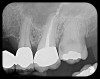

There are two specific types of DIDR sensor systems available to dentists in the marketplace: the hard-wired (HW) sensor and the photostimulable phosphor (PSP) sensor,1,2 also commonly known as phosphor "plates." A desirable feature common to both modalities is the ability to expose either bitewing (BW) or PA radiographic images. The BW radiograph (Figure 1) is usually considered more appropriate for caries detection, whereas the PA (Figure 2) is diagnostic for several different anatomic and pathologic issues.7

Fig 2. Left: PSP vertical PA radiograph of

maxillary bicuspid area demonstrating full root structure, several millimeters of bony anatomy beyond apices and maxillary sinus. Tooth No. 4 may be

traumatized as periodontal ligament is widened. Right: PSP horizontal PA radiograph of maxillary bicuspid area. Tooth No. 12 shows widened apical

periodontal ligament presumably caused by deep restorative filling. Some loss of supporting bone is evident interproximally, especially pronounced

between tooth Nos. 14 and 15.

Figure 2